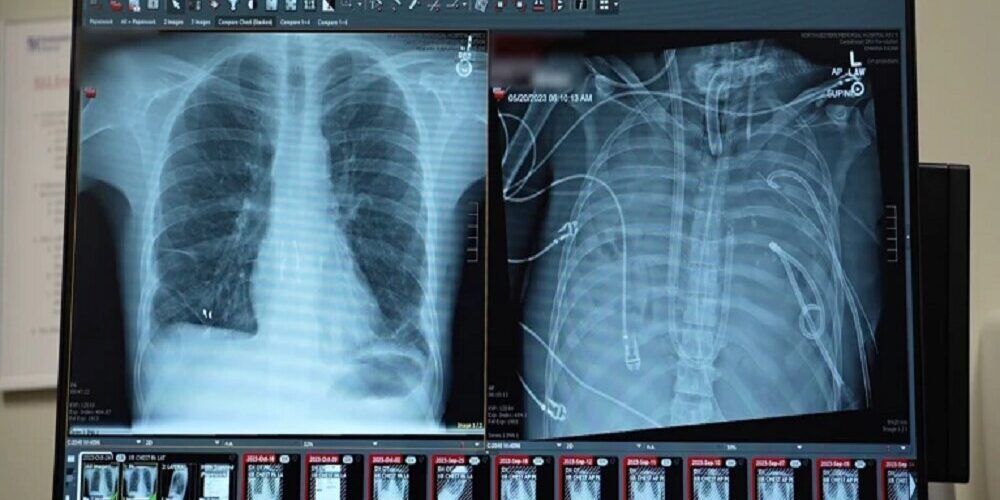

مردی ۴۸ ساعت بدون ریه زنده ماند

به گزارش خبرآنلاین، به نقل از ایسنا، انکیت بهارات، جراح قفسه سینه در دانشکده پزشکی فاینبرگ دانشگاه نورث‌وسترن در شیکاگو، ایلینوی، که به توسعه یک سیستم ... ادامه مطلب